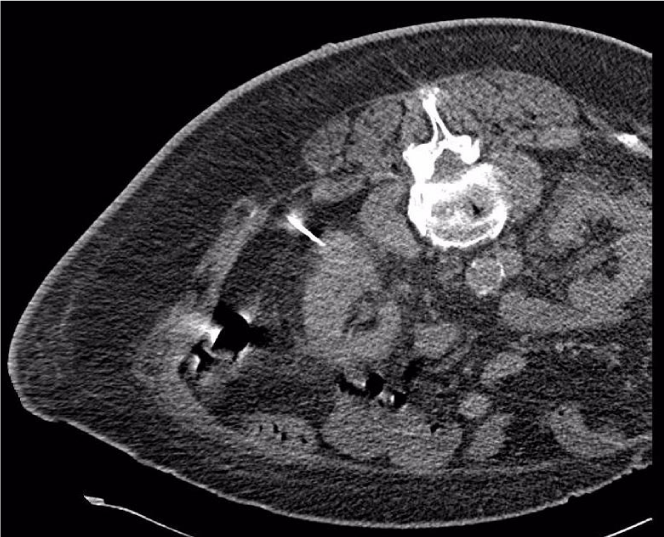

A 17- gauge, 20 cm Neuwave PR probe (NeuWave Medical, Madison, WI) was used for the procedure. After the probe was placed with its tip in the tumor via left posterolateral approach under ultrasound guidance (Figure 2), a CT scan to check position of the probe with tissue-lock revealed a large amount of air in the left flank subcutaneous tissues as well as left perinephric free air (Figure 3). The microwave ablation probe was immediately taken out of the patient. Using Seldinger technique with an 18-gauge needle, an 8 French pigtail drainage catheter was placed into the left flank subcutaneous tissues over an Amplatz guidewire (Figure 4) and the CO2 was aspirated. Subsequently, an 18-gauge needle was advanced into the left perinephric space under CT guidance and a small to moderate volume of the CO2 was aspirated. The ensuing CT scan demonstrated interval decrease in amount of CO2 in the left flank subcutaneous and left perinephric space. The subcutaneous pigtail drainage catheter was removed while the patient was still on the CT table.

Figure 3: Leakage of gas into the left retroperitoneal and subcutaneous spaces (cursor) during ablation with a 17-gauge PR probe (arrow). Note that the tip of the probe (arrow) is moved out of the lesion due to the gaseous expansion of the probe tract.